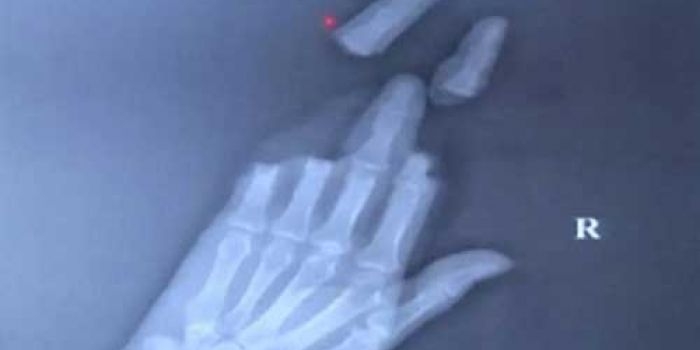

Main Layang-layang, Empat Jari Putus ‘Diiris’ Benang